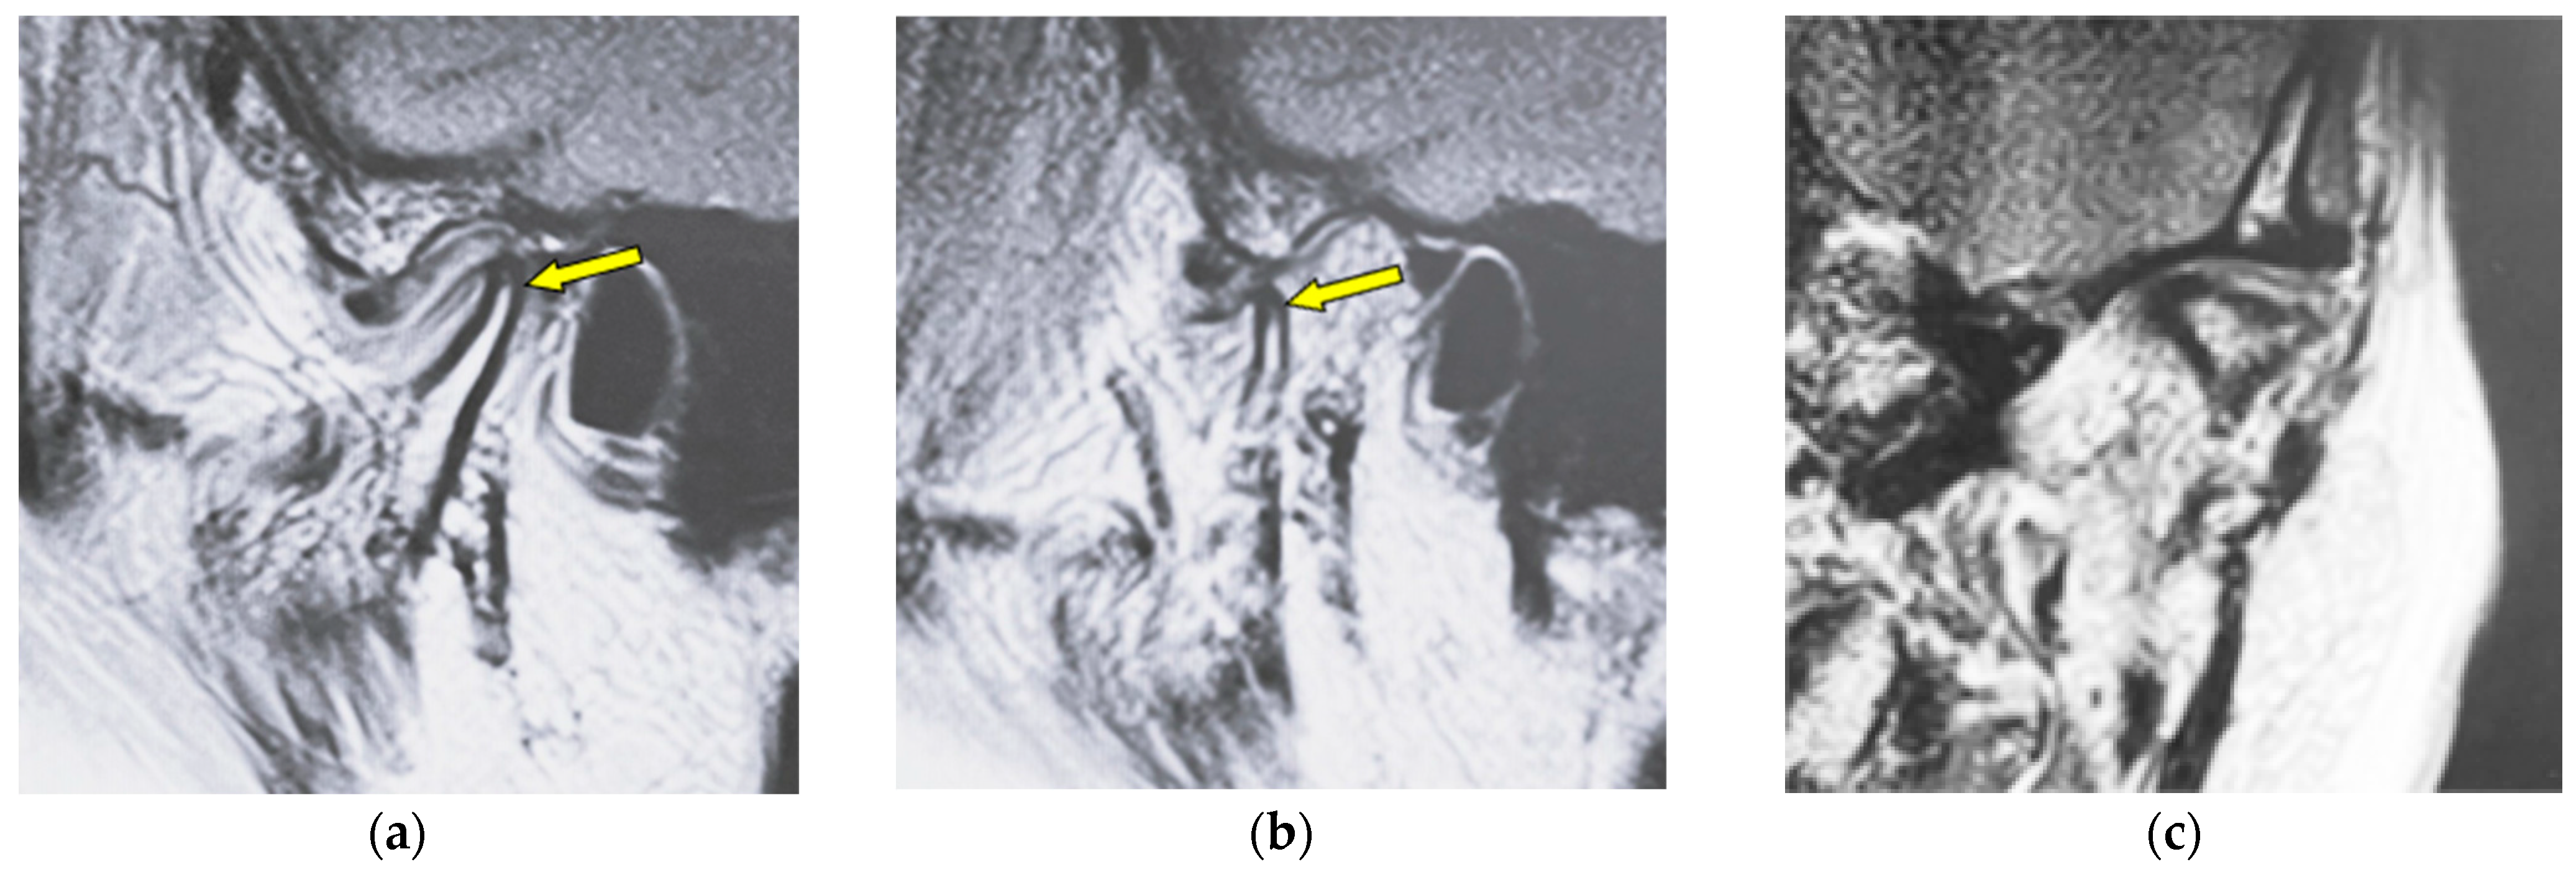

| Atrophy | Reduction in anteroposterior widths in the mandibular condyle without a round form |